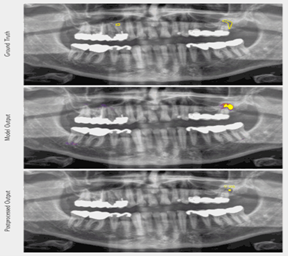

ومن منظور شمولي، قدمت دراسة “نظام متعدد المهام لتشخيص أمراض الأسنان المتعددة في الصور البانورامية باستخدام بنية (Faster R-CNN) لتشخيص عدة أمراض في الصور البانورامية في آن واحد (مثل التسوس وفقدان العظم)، مؤكدة تفوق الأنظمة متعددة المهام في الكفاءة السريرية على النماذج الفردية [9].

الشكل:[3] امثلة على كشف تسوس الاسنان في صور الاختبار.[9]